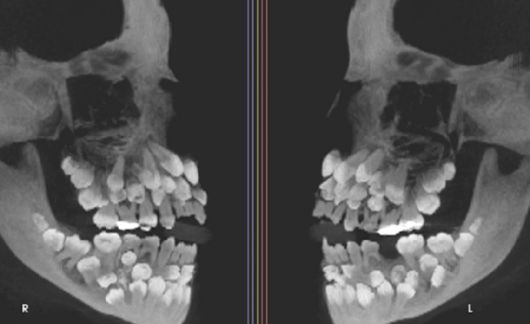

이 소녀는 유치 1개를 발치하기 위해 병원을 찾았다가 엑스레이 촬영 결과 예상치 못한 사실을 발견했다. 유치 18개, 영구치 32개, 과잉치 31개 등 총 81개의 치아가 그의 입 안에 존재했던 것이다.

'치아 81개'를 가진 사례가 학계에 보고됐다. 사진은 소녀의 엑스레이. [사진=미국 치과교정·악안면외과학회지(AJO-DO)] |